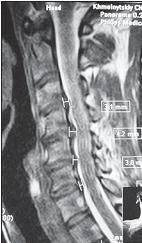

МРТ № 29

На МРТ № 29 наблюдаются протрузии и грыжи межпозвонковых дисков в шейном отделе позвоночника На МРТ № 30 головного мозга этого же пациента наблюдаются очаги демиелинизации вследствие развития нейроинфекции